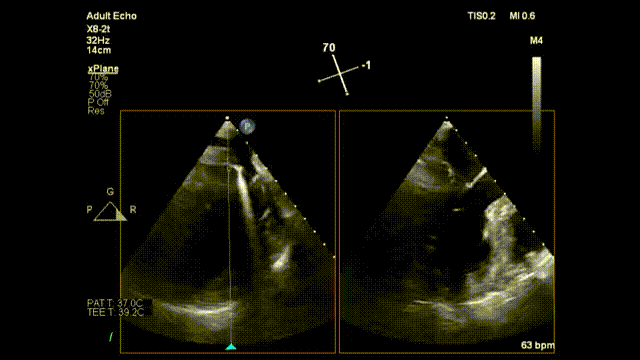

手术过程中,魏来教授使用直径只有3mm(9F)的E-Chord™装置,经心尖穿刺入路,在单纯超声引导下,准确定位,仅用一小时便在P1-P2区植入了3对人工腱索。患者术中心脏不停跳,创伤很小,几乎无出血,术毕二尖瓣返流完全消失。术后患者恢复快,第三天即顺利出院。出院前复查心超,显示左房内径明显缩小至正常范围(由术前45mm缩小至40mm),二尖瓣结构及功能正常,无返流。

术前二尖瓣重度反流

术中器械顶住二尖瓣并击发

术毕二尖瓣反流消失

出院前复查心超二尖瓣无反流